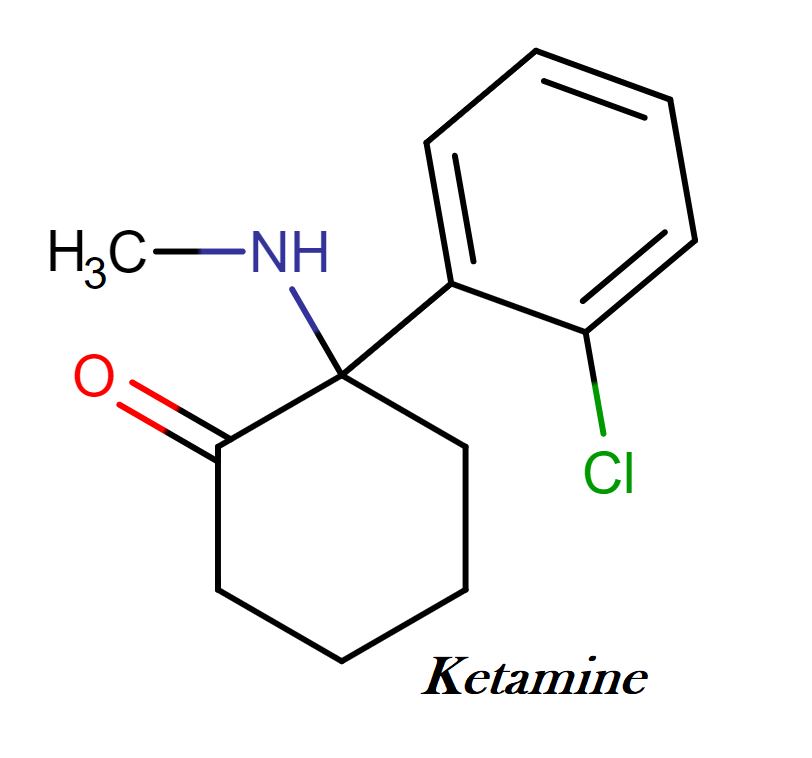

Ketamine: A Brief Overview

Ketamine, first synthesized in 1962, has a long history as an anesthetic and analgesic. During the late 1960s, ketamine was marketed as the dissociative (out-of-body experience) anesthetic, under the name Ketalar and was used to treat soldiers in the Vietnam War. The abuse potential of ketamine was recognized in the early 1970s, but reports of ketamine abuse in human and veterinary medicine did not appear until the early 1980s in Australia and in the early 1990s in the United States. In recent years, it has gained significant attention for its rapid antidepressant effects, particularly in cases of treatment-resistant depression. Ketamine’s primary mechanism of action involves blocking the NMDA receptor for glutamate in the brain, leading to a dissociative state and a cascade of neurochemical changes.

Findings from my own laboratory in 1997 showed that repeated ketamine intake alters the balance between the neurotransmitters dopamine and serotonin in the brain. Ketamine’s interaction with the NMDA receptor for glutamate triggers a surge in glutamate, a neurotransmitter vital for learning and memory. This glutamate surge is thought to promote the growth of new synapses and neural connections, particularly in brain regions associated with mood regulation. Additionally, ketamine disrupts the default mode network (DMN), a brain network linked to rumination and self-referential thinking, which may contribute to its antidepressant effects. Research also suggests that ketamine may stimulate neurogenesis (the growth of new neurons) and promote neuroplasticity (changes in neural connections).

The Perils of Ketamine

While ketamine holds immense therapeutic promise, it is crucial to acknowledge its risks. Ketamine can cause dissociative effects, hallucinations, and other adverse reactions. Moreover, it has a potential for abuse and addiction, as tragically illustrated by Matthew Perry’s case. Long-term effects of ketamine use on brain function and cognition remain an area of ongoing research.